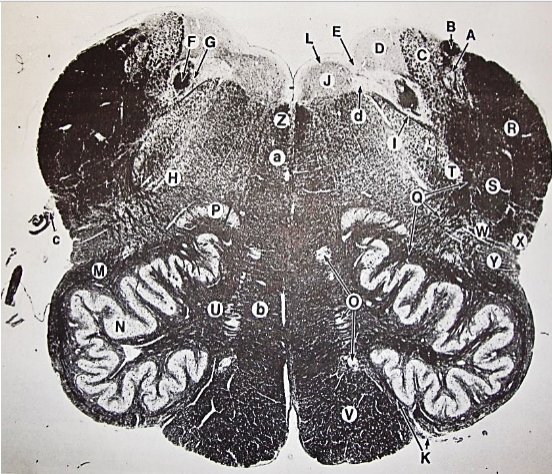

A

Fasciculus gracilis

B

gracile nucleus

C

fasciculus cuneatus

D

cuneate nucleus

E

spinal trigeminal tract

F+G collectively

spinal trigeminal nucleus

H

accessory nucleus

I

pyramidal decussation

J

rubrospinal tract

K

posterior spinocerebellar tract

L

anterior spinocerebellar tract

M

lateral spinothalamic tract

N

anterior spinothalamic tract

O

lateral vestibulospinal tract

P

medial longitudinal fasciculus

Q

tectospinal tract